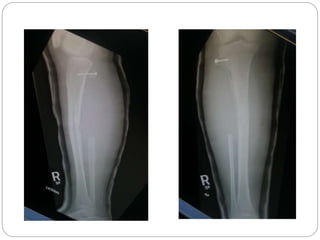

This document discusses 8 oncology cases. Case 1 involves a 40-year old female with right knee pain. Case 2 is a 28-year old male with a left subtrochantric fracture from a MVA who is now experiencing increasing left knee pain and swelling. Biopsy results showed high-grade osteosarcoma. Case 3 is a 30-year old female with breast cancer and bone metastases causing bilateral hip pain.